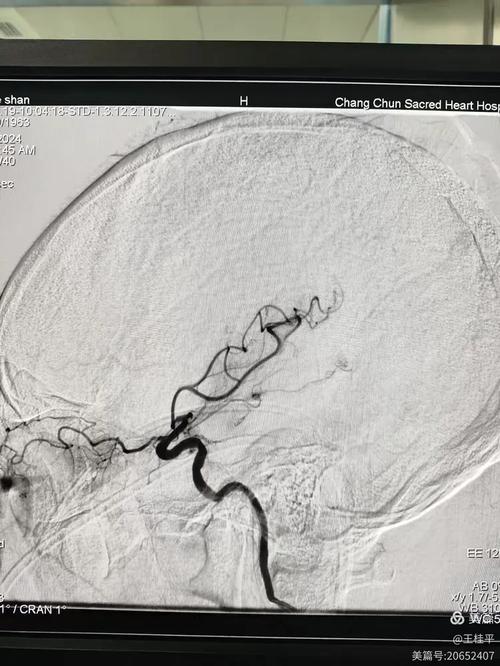

- CTA/MRA (CT血管造影/磁共振血管造影): 这是关键检查!可以直接看到哪条血管堵了、堵塞的位置和严重程度,是评估是否适合进行取栓手术的“金标准”。

- 动脉取栓: 如果是大血管堵塞(如您描述的情况),即使过了静脉溶栓时间窗,只要影像评估显示有可挽救的脑组织,患者会被紧急送到介入导管室,医生会从大腿根部(股动脉)插入一根导管,在血管内导航到堵塞部位,然后用取栓支架或抽吸导管将血栓直接取出,这是目前治疗大血管闭塞最有效的方法。